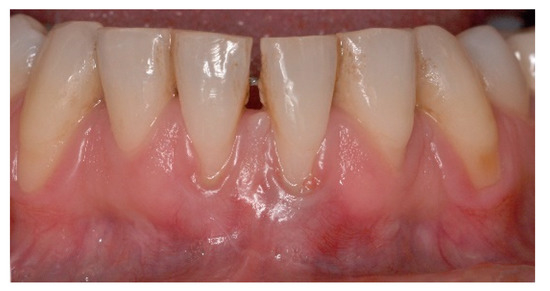

5. Materials and Methods

6. Results